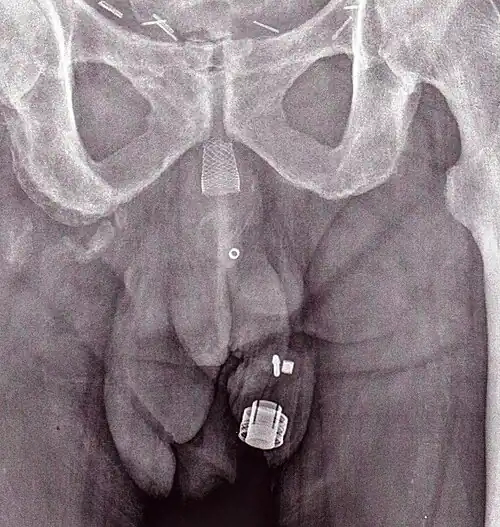

An X-ray image of implanted ZSI 375. The device is deactivated – the spring is compressed below the top of the cylinder. Patient is incontinent. -